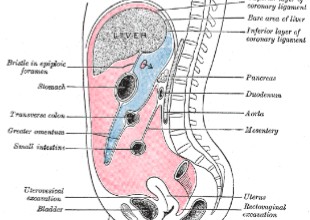

What is the name of the area in ‘red’?

Blue?

Greater sac

Lesser sac

Where does the pancreas lie in relation to the posterior wall of the stomach?

Posterior